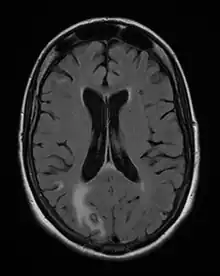

Acute toxoplasmosis is often asymptomatic in healthy adults.[13][14] However, symptoms may manifest and are often influenza-like: swollen lymph nodes, headaches, fever, and fatigue,[15] or muscle aches and pains that last for a month or more. It is rare for a human with a fully functioning immune system to develop severe symptoms following infection. People with weakened immune systems are likely to experience headache, confusion, poor coordination, seizures, lung problems that may resemble tuberculosis or Pneumocystis jirovecii pneumonia (a common opportunistic infection that occurs in people with AIDS), or chorioretinitis caused by severe inflammation of the retina (ocular toxoplasmosis).[15] Young children and immunocompromised people, such as those with HIV/AIDS, those taking certain types of chemotherapy, or those who have recently received an organ transplant, may develop severe toxoplasmosis. This can cause damage to the brain (encephalitis) or the eyes (necrotizing retinochoroiditis).[16] Infants infected via placental transmission may be born with either of these problems, or with nasal malformations, although these complications are rare in newborns. The toxoplasmic trophozoites causing acute toxoplasmosis are referred to as tachyzoites, and are typically found in various tissues and body fluids, but rarely in blood or cerebrospinal fluid.[17]

Due to the absence of obvious symptoms,[13][14] hosts easily become infected with T. gondii and develop toxoplasmosis without knowing it. Although mild, flu-like symptoms occasionally occur during the first few weeks following exposure, infection with T. gondii produces no readily observable symptoms in healthy human adults.[7][20] In most immunocompetent people, the infection enters a latent phase, during which only bradyzoites (in tissue cysts) are present;[21] these tissue cysts and even lesions can occur in the retinas, alveolar lining of the lungs (where an acute infection may mimic a Pneumocystis jirovecii infection), heart, skeletal muscle, and the central nervous system (CNS), including the brain.[22] Cysts form in the CNS (brain tissue) upon infection with T. gondii and persist for the lifetime of the host.[23] Most infants who are infected while in the womb have no symptoms at birth, but may develop symptoms later in life.[24]

Pregnancy precautions

Congenital toxoplasmosis is a specific form of toxoplasmosis in which an unborn fetus is infected via the placenta.[55] Congenital toxoplasmosis is associated with fetal death and miscarriage, and in infants, it is associated with hydrocephalus, cerebral calcifications and chorioretinitis, leading to encephalopathy and possibly blindness.[6] If a woman receives her first exposure to T. gondii while pregnant, the fetus is at particular risk.[6] A simple blood draw at the first prenatal doctor visit can determine whether or not a woman has had previous exposure and therefore whether or not she is at risk. A positive antibody titer indicates previous exposure and immunity, and largely ensures the unborn fetus' safety.

Diagnosis of toxoplasmosis in humans is made by biological, serological, histological, or molecular methods, or by some combination of the above.[62] Toxoplasmosis can be difficult to distinguish from primary central nervous system lymphoma. It mimics several other infectious diseases so clinical signs are non-specific and are not sufficiently characteristic for a definite diagnosis. As a result, the possibility of an alternative diagnosis is supported by a failed trial of antimicrobial therapy (pyrimethamine, sulfadiazine, and folinic acid (USAN: leucovorin)), i.e., if the drugs produce no effect clinically and no improvement on repeat imaging.

The classic triad of congenital toxoplasmosis includes: chorioretinitis, hydrocephalus, and intracranial arteriosclerosis.[75] Other consequences include sensorineural deafness, seizures, and intellectual disability.[76]